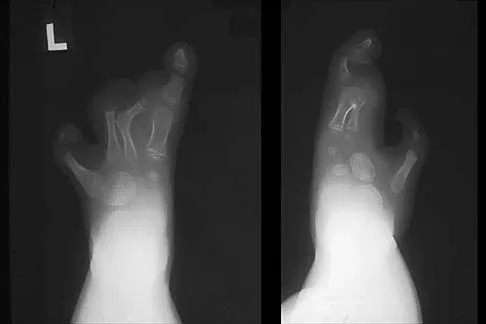

A 26-year-old ballet dancer reports posterolateral ankle pain, especially with maximal plantar flexion. Examination reveals maximal tenderness just posterior to the lateral malleolus, and symptoms are heightened with forced passive plantar flexion. Radiographs are shown in Figures 42a and 42b. What is the most likely cause of the patient's symptoms?

Explanation